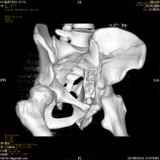

Уважаемые коллеги! Хотелось бы услышать совет по тактике лечения представлленого больного.Поступил после лечения в одном изотделений области. Травма 2,5 месяца назад. После выведенияиз шока был произведен остеосинтез перелома бедра, предплечья, до перевода к нам проводилосьвытяжение по оси шейки бедра за стержень, введенный в большой вертел. На сегодня деформацияригидна, клинически мобильности не определяется. Заранее признателен. P.S. Данный вид травм не включен в перечень "высокотехнологичных операций", направить длялечения по квотам Минздрава очень сложно.

Привет, Леонид. Оскольчатый высокий двухколонный перелом в такие сроки трогать не надо, т.к. это про такие переломы сказано: "кто с ножом на Ж. пойдет тот в ней и останется...".